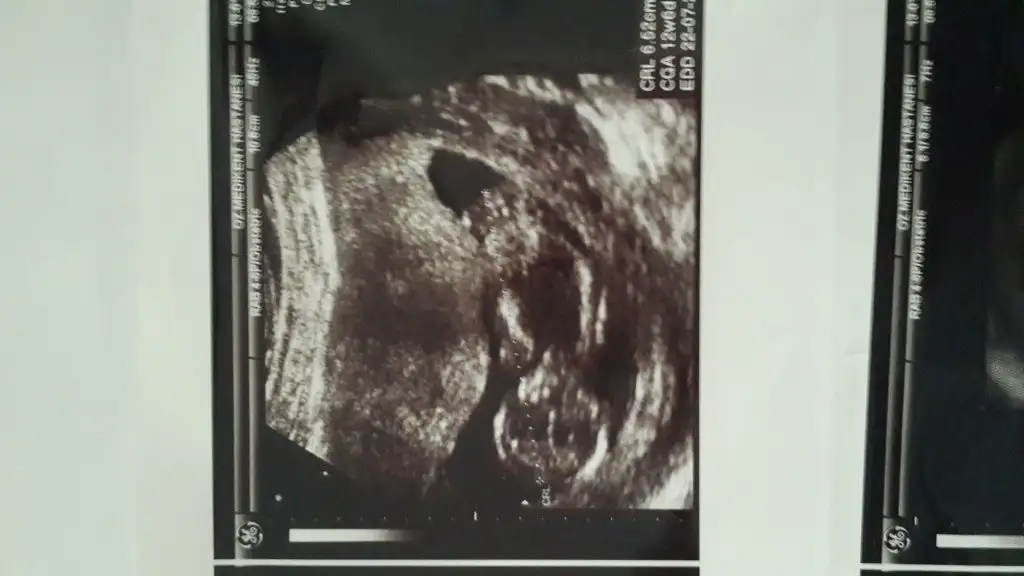

Tesekkur ederim cnm.bir kizim var 5 yasinda.acikcasi icime hep erkekmis gbi gelio ama hayirlisi bakalim.ikili teste gidicem 15 gun sonra bide o zamn bakalim.belki pipişi goruruzCanim daha cook kucuk ama keseye gore bakarsak kese yuvarlak ve saga yakin yabu kizz...

Kac haftalik bu bebis ayrintili testte kacinci haftada girdjn canim hic belli deil kucuk...Kizlar ya ayrintili teste girdim dr kiz dedi bugun kendi doktorum erkek dedi varmi resimden anlayabilecek oln

11 de ayrintiliya girdim 14te doktor muayene etti en son halini atiyorm canmKac haftalik bu bebis ayrintili testte kacinci haftada girdjn canim hic belli deil kucuk...

gönlumden gecen ve hissettigim hep kizdi ama kendi doktorum da oyle deyince gerci saglikli olsun baska bisey istemyrmKız bu benim bence

Bacakları kapalı gibi ama doktor görmüştür herhalde :) yatışı çok tatlı ama maşAllah :)Tabi cnm . Sağol canim